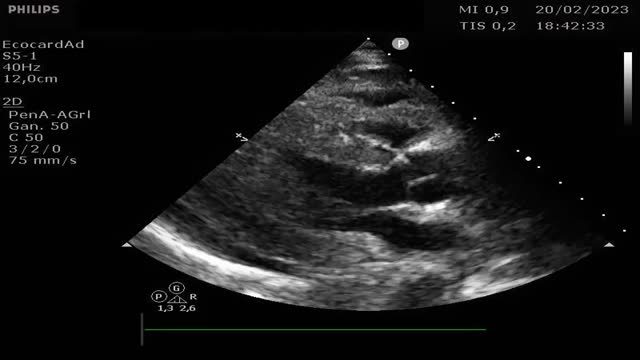

Se trata de una mujer de 41 años con deficiencia humoral y gammapatía monoclonal IgG lambda, que acude al servicio de Urgencias con fiebre y debilidad, siendo diagnosticada de infección respiratoria secundaria a Influenzae A. Veinticuatro horas después ingresa en el servicio de Medicina Intensiva por hipotensión severa, con necesidad de noradrenalina hasta 0,5 ug/kg/min, hipoalbuminemia y hemoconcentración. Se estableció el diagnóstico de síndrome de fuga capilar sistémica con edema intramiocárdico. El síndrome de fuga capilar sistémica es una condición caracterizada por la fuga de plasma y proteínas al compartimento intersticial, y se asocia con gammapatía monoclonal y frecuentemente aparece después de una infección del tracto respiratorio superior, siendo el edema intramiocárdico una complicación poco frecuente. En nuestra paciente, se realizó un ecocardiograma transtorácico al ingreso, mostrando una función ventricular sistólica dentro del límite inferior de la normalidad (FEVI 50-55%), con comportamiento restrictivo, además se evidencia un engrosamiento difuso del miocardio: eje largo paraesternal (fig. 1 y vídeo A), eje corto paraesternal a nivel apical (fig. 2), y plano apical cuatro cámaras (fig. 3), probablemente secundario a edema intramiocárdico, ya que un ecocardiograma transtorácico realizado 1 mes antes mostró grosores normales, eje largo paraesternal (fig. 4). Se prescribió tratamiento con inmunoglobulinas y corticosteroides, pero lamentablemente la paciente falleció 24 horas después del ingreso debido a un shock refractario.